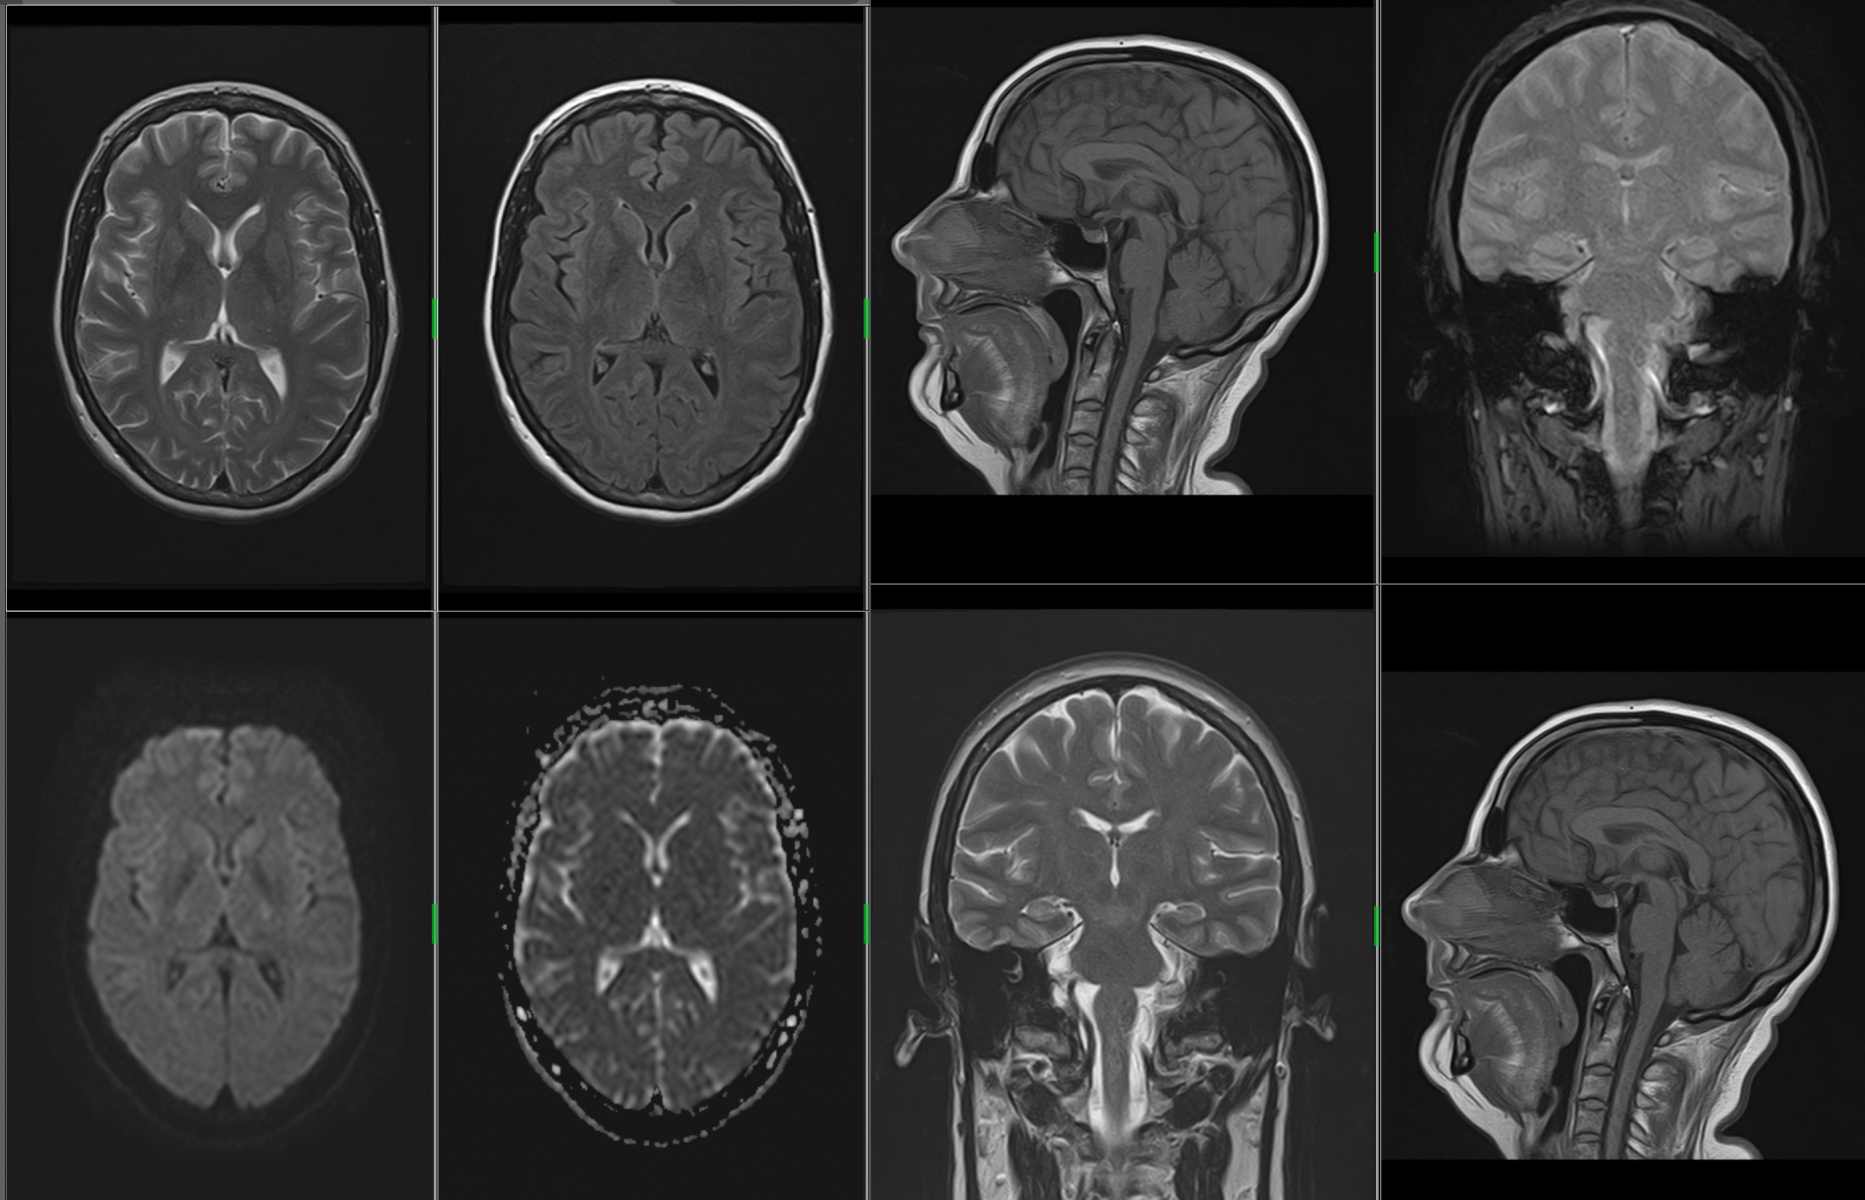

MR mozku

Nádorová onemocnění, zánětlivá onemocnění – zvláště pak demyelinizační onemocnění bílé hmoty (roztroušená skleróza), epilepsie, cévní onemocnění (malformace, aneuryzmata), neurodegenerativní onemocnění, vrozené vady, hydrocephalus všech typů, bolesti hlavy, psychické změny (včetně psychotických onemocnění), onemocnění hypofýzy a mozkových nervů, následky úrazů hlavy (zvláště se zaměřením na difusní axonální poranění a rozpadové produkty hemoglobinu (ferritin a hemosiderin)), MR je možno provést u akutních krvácení a k posouzení fraktur lebky, ale zde je vhodnější provedení CT.